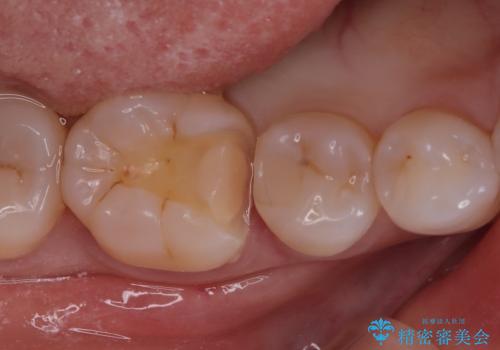

- 主訴:右下の奥歯がたまに冷たい物や甘いものでしみる

右下6番目の歯に大きめのう蝕を認め、形態の再現性を考えインレーでの治療となりました。

右下6の近心にう蝕が認められう蝕の範囲が大きかったため、歯冠形態の再現性の高いインレーでの修復とし、材質は審美性、清掃性に優れたセラミックを選択しました。